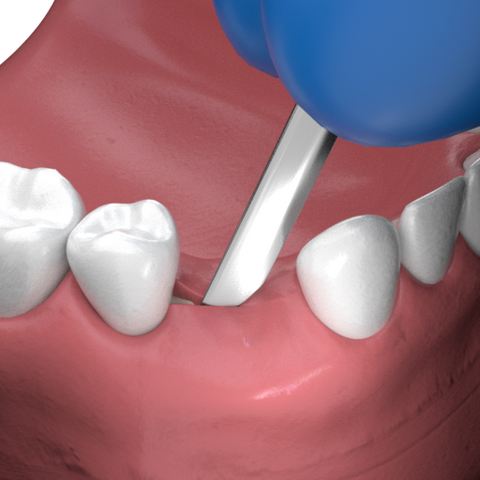

Bone Profiler Tool Procedure